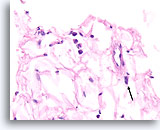

Lobulair carcinoom, Borst FNA, celblok.

Lobulaire carcinoomcellen lijken in het stromaweefsel te zijn ingebed, zodat de indruk wordt gewekt van hypercellulariteit. Dit kan de reden zijn waarom cytologische preparaten van een lobulair carcinoom vaak weinig maligne cellen tonen.

20X

Lobulair carcinoom, Borst FNA, celblok.

Lobulaire carcinoomcellen lijken in het stromaweefsel te zijn ingebed, zodat de indruk wordt gewekt van hypercellulariteit. Dit kan de reden zijn waarom cytologische preparaten van een lobulair carcinoom vaak weinig maligne cellen tonen.

20X